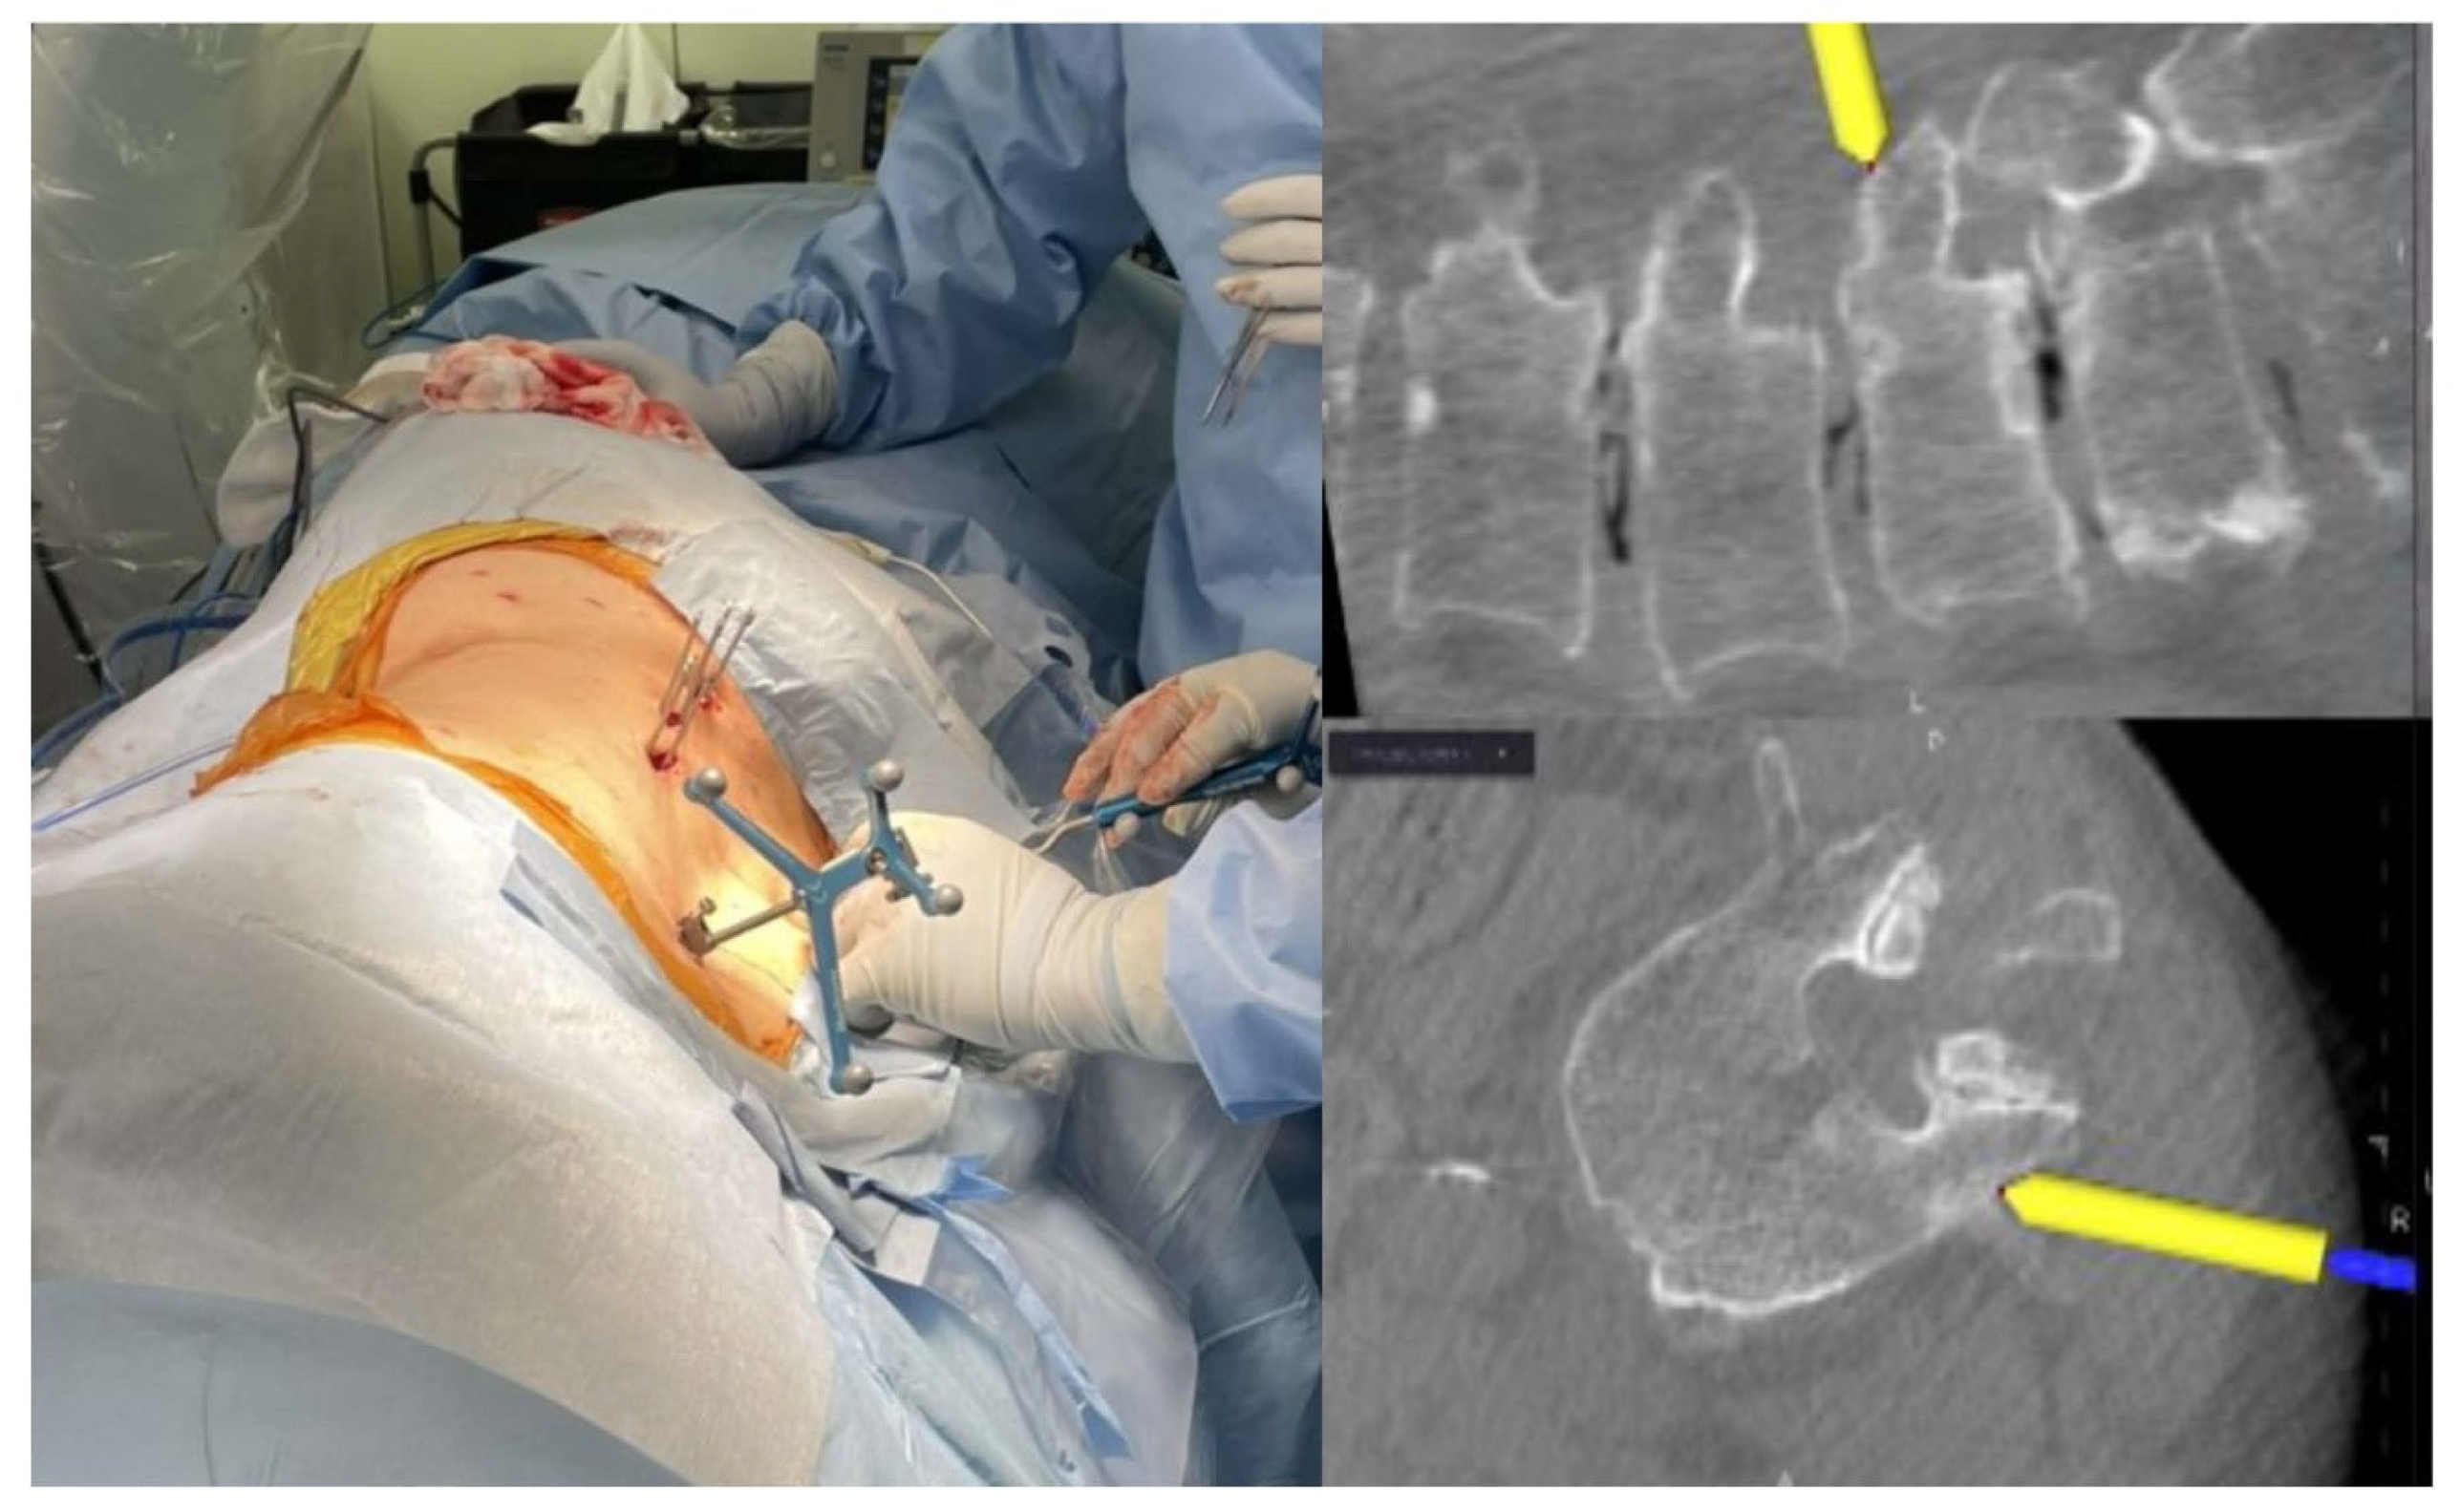

The patients were placed in an oblique position of approximately 45° on a Jackson table, fixing the trunk more firmly compared to the lateral decubitus position with medical tape to prevent the trunk from shifting position during the bed rotation (Figure 1). Fixation of the reference frame was achieved by clamping the spinous process at one or two spinal levels superior to the fusion level. First, two surgeons performed posterior PPS fixation from the ventral and dorsal sides to avoid navigation errors caused by intervertebral expansion and/or correction associated with the cage insertion of the LIF. Following PPS fixation in an oblique position, the patient was repositioned to a lateral decubitus position using bed rotation without resetting surgical drapes and sterile instrument fields. Then, the LLIF procedure was performed from the patient’s ventral side using intraoperative CT image-guidance navigation in a lateral decubitus position.

Figure 1.

Photographs and the intraoperative CT navigation screen during PPS insertion in the oblique group, where the patients were placed in an oblique position of approximately 45° on a Jackson table. PPS, percutaneous pedicle screw. Yellow arrow denote Navigation pointer.